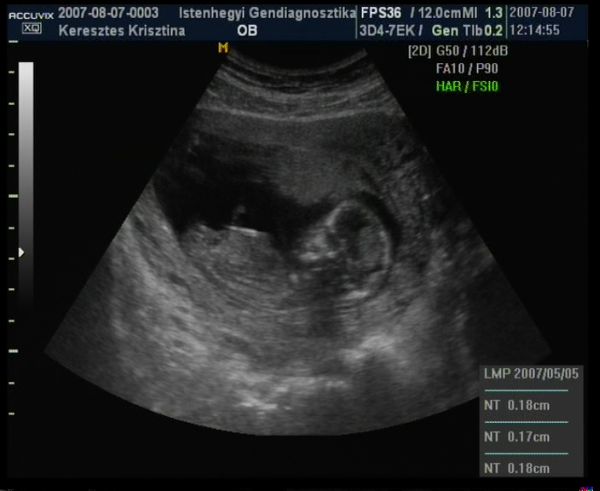

Lányok!

Ti voltatok az Istenhegyi klinikán integrált teszten? Engem Konc elküldött és holnap du. 1-re kaptam időpontot. Ha jól tudom, akkor ez vérvételből és UH-ból áll - ez utóbbi gondolom, még mindig hüvelyi.. Ha volt valamelyikőtök, mikorra lett eredmény?

Én kombinált teszten voltam, de az integrált is hasonló. Ha a keresőbe beütöd a géndiagnosztika szót, az első vagy második találat az Istenhegyis oldal. Ott mindent megtalálsz részletesen az integrált tesztről. A kombináltnál volt egy vérvétel és egy hasi uh, mire végeztem addigra az eredmények is megvoltak csak egy kicsit kellett várni. Az egész kb. 1-1.5 óra volt. És 28000 Ft.